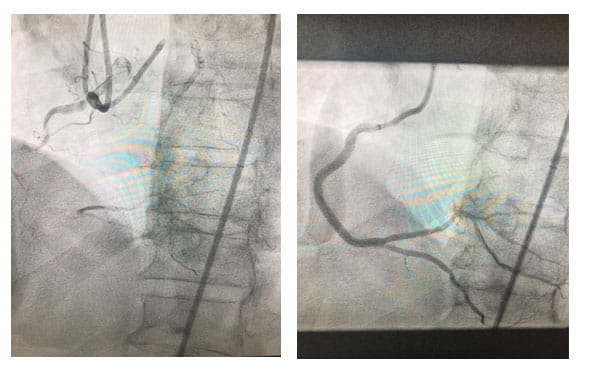

Before and after stent implantation of RCALeft image: Before stent implantation of RCA. Right image: After stent implantation of RCA.